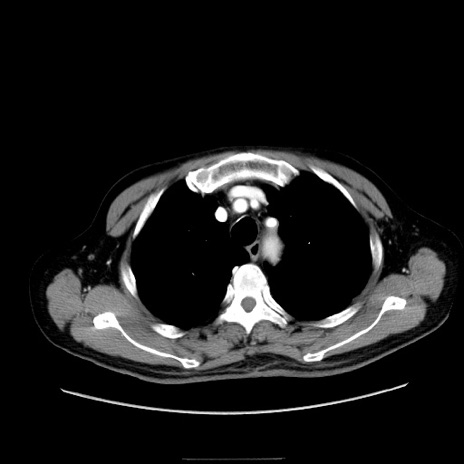

症例30(横断像)

【症例】80歳代男性

【主訴】臍周囲痛

【現病歴】約6時間前から臍下部痛が出現。次第に腹部膨隆・背部痛も生じてきたため来院。背部痛の場所は変化しない。

【身体所見】意識清明、BT 36.3℃、BP  131/87mmHg、P 87bpm、SpO2 100%(RA)、臍周囲自発痛・圧痛あり、反跳痛なし、自発痛部位に一致して板状硬あり、腹部膨隆、腸雑音減弱、CVA tenderness両側陰性。

【データ】WBC 19600、CRP 0.33